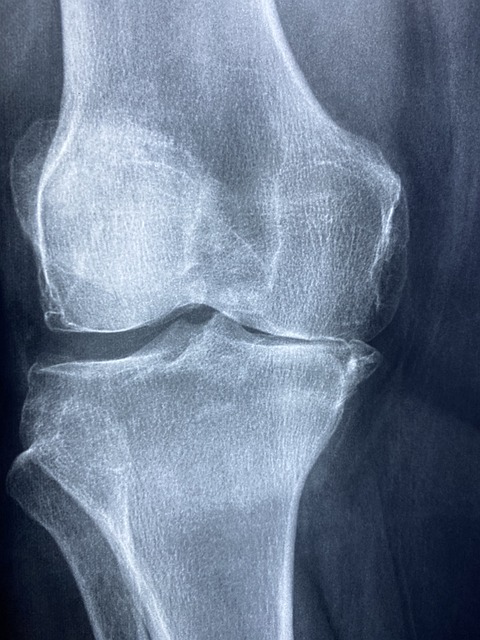

퇴행성 관절염은 일반적으로 나이가 들면서 발생합니다. 이 형태의 관절염은 관절의 연골이 마모되면서 점차 악화되는 현상인데요, 이는 오랜 시간 동안의 반복적인 스트레스나 과사용으로 인해 발생할 수 있습니다. 퇴행성 관절염은 무릎, 엉덩이, 손가락에 주로 발생하며, 증상으로는 통증, 뻣뻣함, 움직일 때 소리가 나는 등의 특징이 있습니다.

퇴행성 관절염의 초기 단계에서 나타나는 증상은 매우 미미하게 시작됩니다. 예를 들어, 아침에 일어났을 때 관절이 뻣뻣한 느낌이 들 수 있습니다. 이는 걷거나 움직일 때 점차 풀리기도 하지만, 단순한 피로나 스트레스로 여겨질 수 있어 종종 간과됩니다. 그러나 이런 초기 증상을 무시하지 말고 적극적으로 관리할 필요가 있습니다.